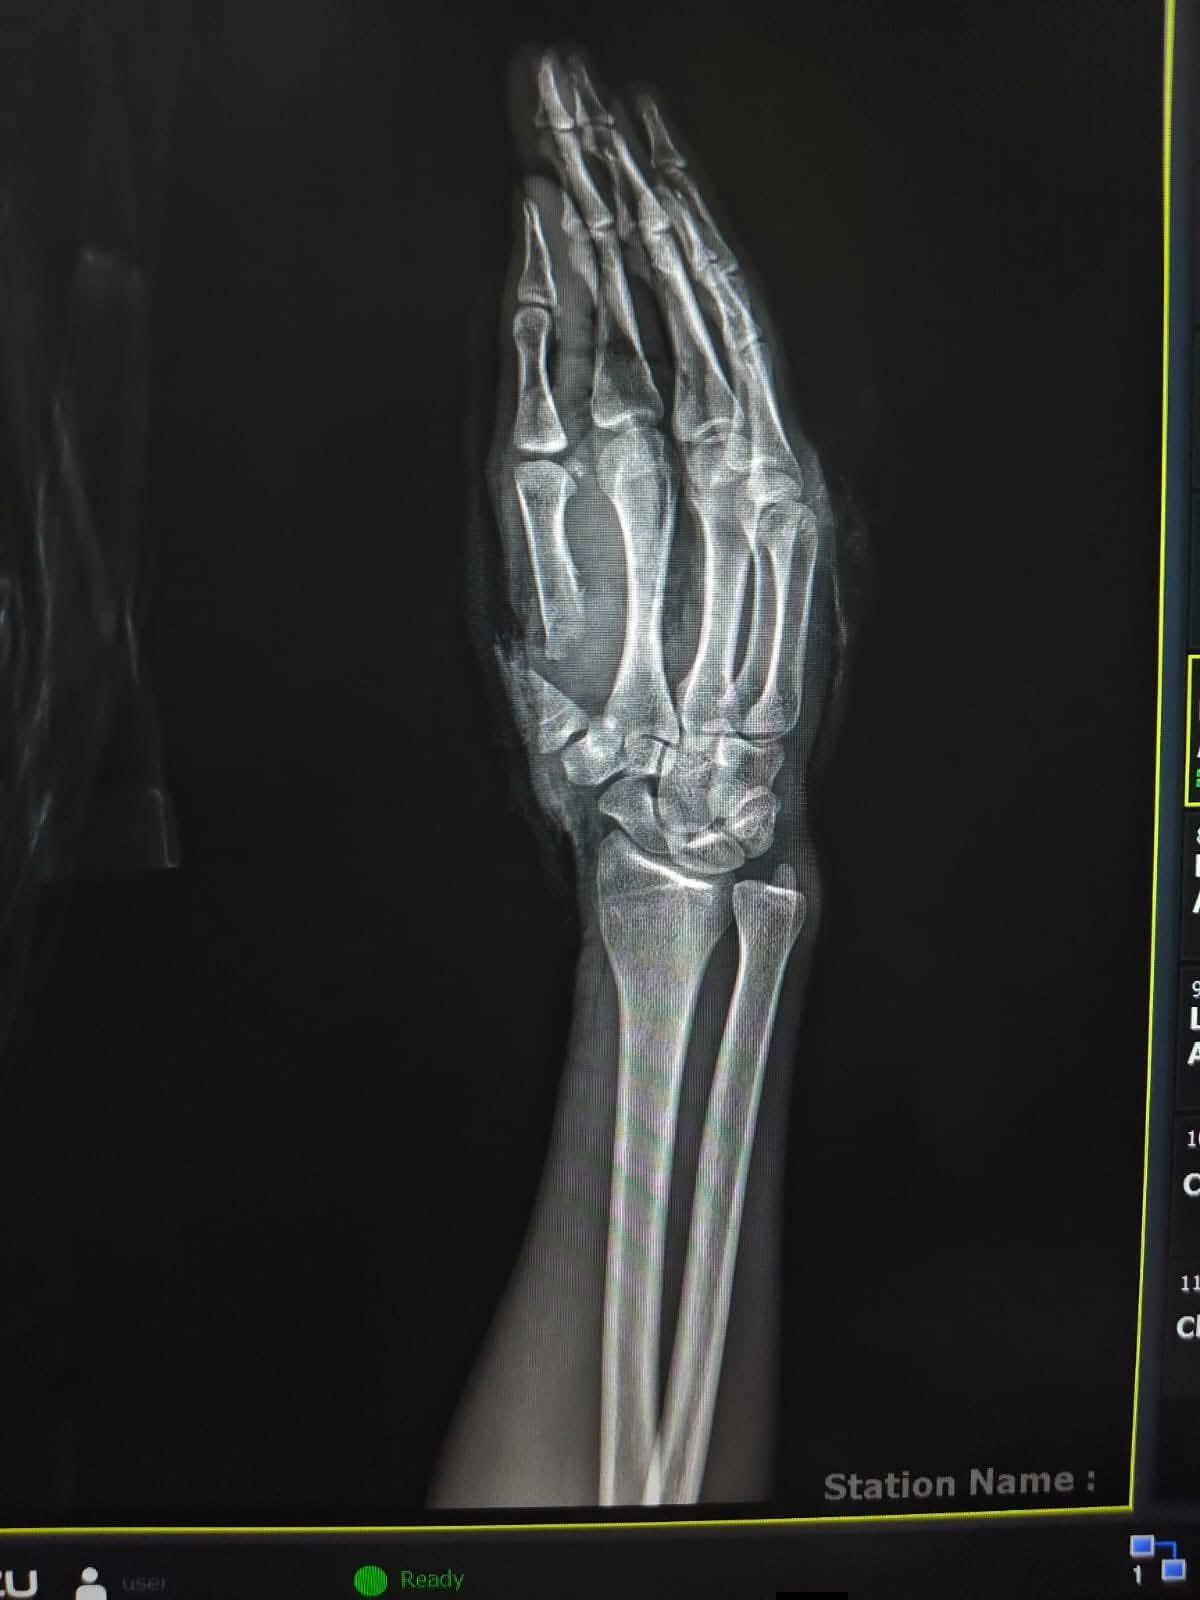

أعلنت وزارة التعليم العالي والبحث العلمي عن نجاح فريق وحدة الجراحات الميكروسكوبية بمستشفى سوهاج الجامعي في إنقاذ شاب يبلغ من العمر 26 عامًا، عقب تعرضه لبتر كامل في إصبع الإبهام نتيجة اعتداء بسلاح أبيض.

وأوضح البيان أن الفريق الطبي أجرى جراحة ميكروسكوبية دقيقة استمرت نحو 6 ساعات، تم خلالها إعادة توصيل الشرايين والأوردة والأعصاب، إلى جانب تثبيت العظام، بما أسهم في إنقاذ الإصبع واستعادة وظيفته الحيوية.